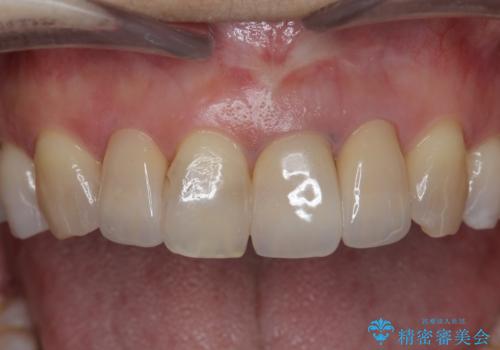

周囲の歯に調和したセラミッククラウンを作製し、審美性を大幅に向上させることができました。

- 39.6万円(ジルコニアクラウン×3・仮歯×3)費用は治療当時の料金となります